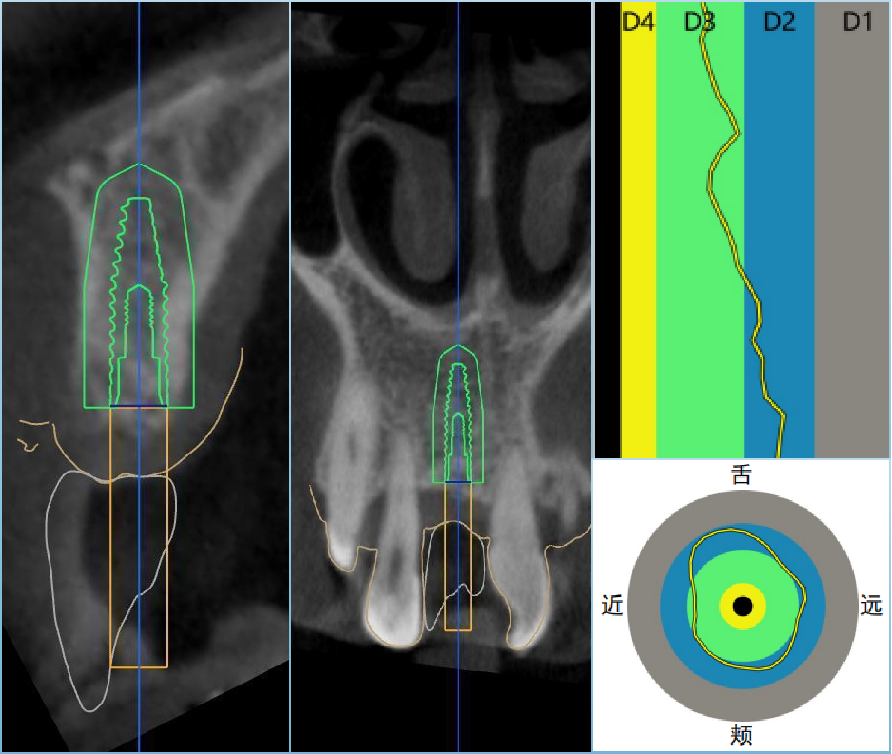

真实案例

TRUE CASE